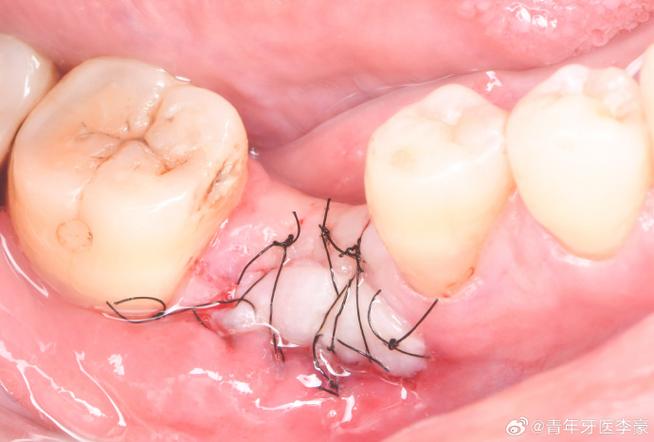

骨粉植入后的稳定性依赖于与骨床的紧密贴合及周围组织的固定,若术中骨粉填塞不均匀、与骨床结合不紧密,或缝合时张力不足、缝线松脱,可能导致骨粉在咀嚼、漱口等外力作用下移位甚至掉出,术区出血若未完全控制,形成血肿压迫骨粉,也可能使其脱离原位。

- 缝合加固:采用可吸收缝线严密缝合牙龈,确保缝合张力适中,避免骨粉暴露。